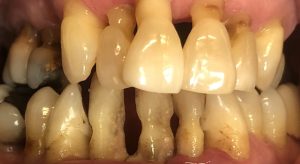

Comprehensive Approach to Upper and Lower Anterior Teeth Removal with Lower Bridge and Upper Implants with Temporary Denture

The management of anterior teeth requiring extraction, especially when combined with prosthetic rehabilitation, requires careful planning to balance function, esthetics, and patient comfort. A treatment plan involving the removal of both upper and lower anterior teeth, placement of a lower bridge, upper implants, and a temporary denture is a complex but effective approach.

- Clinical Examination: Assess periodontal status, tooth mobility, occlusion, and esthetic requirements.

Step 2: Tooth Extraction

- Upper and Lower Anterior Teeth Removal:

Extractions are performed atraumatically to preserve alveolar bone for future implant placement and bridge support. Care is taken to avoid excessive trauma, particularly in the anterior maxilla, which is critical for esthetics. - Hemostasis and Socket Management: